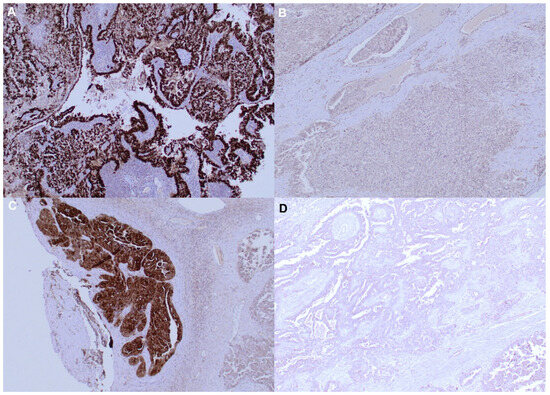

3.2. Immunohistochemistry

- Schultz-Thater, E.; Piscuoglio, S.; Iezzi, G.; Le Magnen, C.; Zajac, P.; Carafa, V.; Terracciano, L.; Tornillo, L.; Spagnoli, G.C. MAGE-A10 is a nuclear protein frequently expressed in high percentages of tumor cells in lung, skin and urothelial malignancies. Int. J. Cancer 2011, 129, 1137–1148. [Google Scholar] [CrossRef] [PubMed]